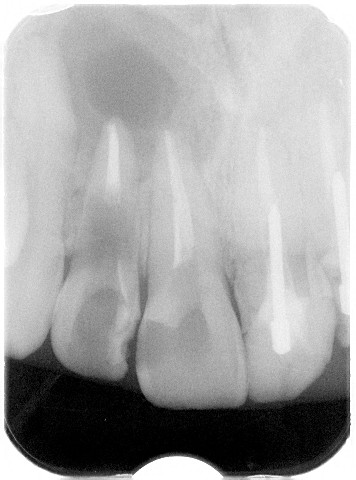

根管を開放されて3年後のデンタルX線写真

やはり相当のダメージを負っています。根尖部の骨がピンポン玉くらいなくなっています。

体の内部に細菌が侵入すると必ず炎症反応が起こります。炎症反応とは体の防御反応なので細菌と白血球の戦いが局所で起こります。その結果白血球の死骸である膿が局所で溜まります。上のレントゲンでは炎症の結果、局所の骨がピンポン玉の大きさで失われました。